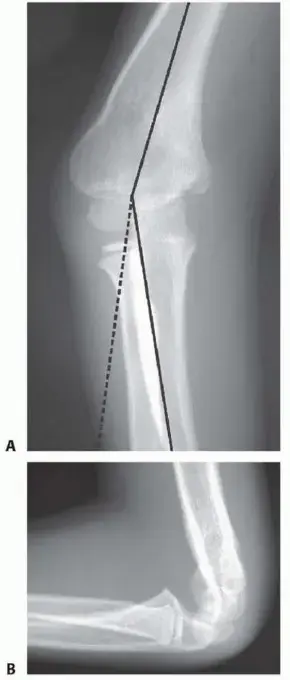

انحراف المرفق الأروح هو تشوه في الجزء السفلي من عظم العضد (العظم الرئيسي في الذراع العلوية) يؤدي إلى تغيير في الزاوية الطبيعية التي يصنعها المرفق بين الذراع والساعد. بشكل طبيعي، يكون المرفق مائلاً قليلاً إلى الخارج عند فرده (تُعرف هذه الزاوية بزاوية الحمل أو Carrying Angle). في حالة المرفق الأروح، ينحرف الساعد إلى الداخل باتجاه الجسم بدلاً من الخارج، مما يعطي الذراع مظهرًا "منحرفًا" أو "على شكل بندقية" (Gunstock Deformity).

- المظهر "المنحرف" أو "شكل البندقية": هذا هو العرض الأكثر وضوحًا وشيوعًا. عند فرد الذراع، يبدو الساعد مائلاً إلى الداخل باتجاه الجسم بدلاً من أن يكون مائلاً قليلاً إلى الخارج. يُعرف هذا طبيًا باسم "تشوه قمة البندقية" (Gunstock Deformity).

- الأشعة السينية (X-rays): هي الفحص الأولي والأكثر أهمية. تُؤخذ صور بالأشعة السينية للمرفق من زوايا مختلفة (أمامية خلفية وجانبية) للذراع المصابة، وغالبًا ما تُؤخذ أيضًا للذراع السليمة للمقارنة. تسمح الأشعة السينية بتقييم بنية العظام، وتحديد درجة الانحراف الزاوي بدقة، وتحديد أي مشاكل في التئام العظام أو تشوهات أخرى.